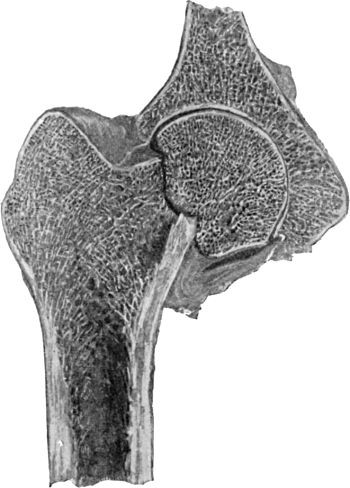

222 119.Arthritis Deformans, showing erosion of Cartilage and lipping of Articular Edge of Head of Femur

225 120.Upper End of Femur in advanced Arthritis Deformans of Hip